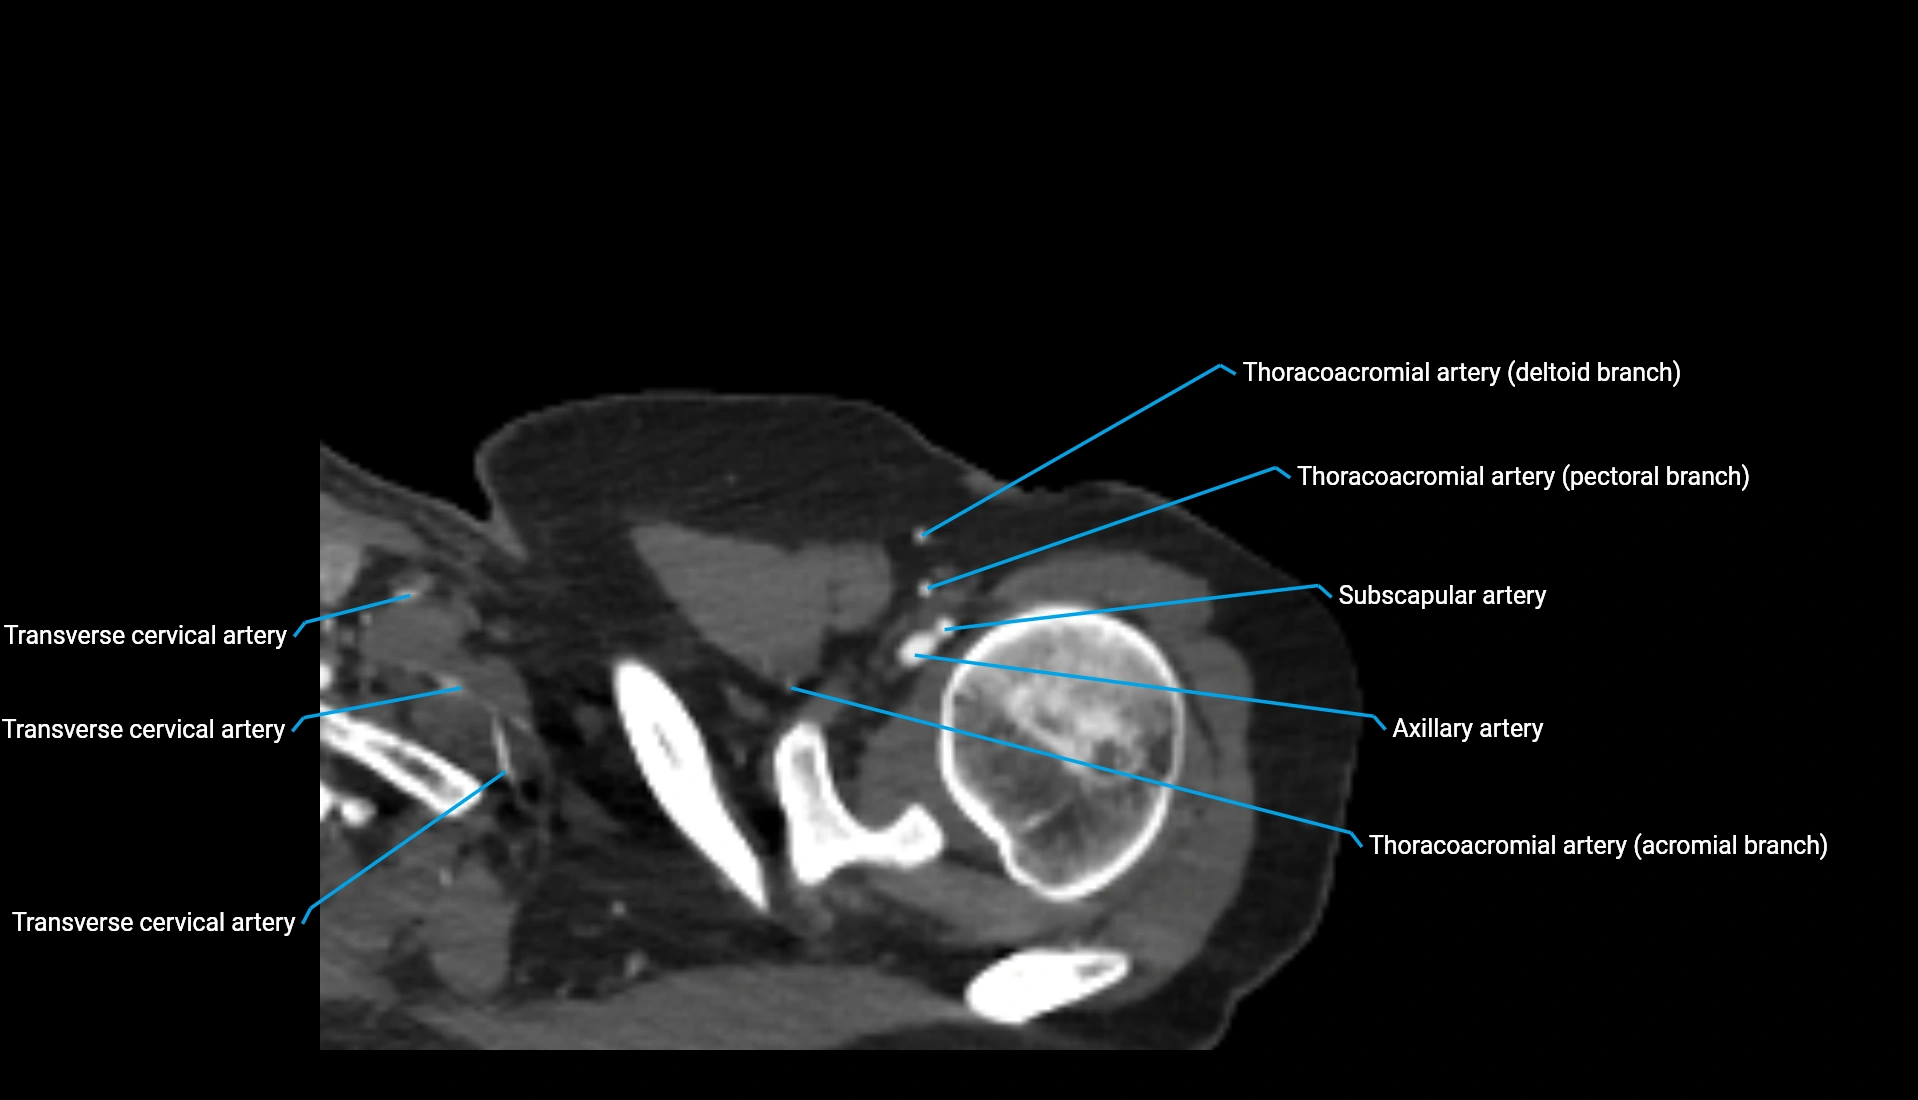

CT Appearance

Non-Contrast CT:

• Cortex: High-density, sharply defined

• Subchondral bone: Dense cancellous matrix

• Articular surface: Smooth concave contour articulating with the capitellum

• Excellent for evaluating bone integrity, alignment, and subtle fractures

Post-Contrast CT:

• Bone: No enhancement

• Joint capsule and synovium: Mild enhancement outlining the joint

• Improves contrast between soft tissues and bony margins

• Useful in detecting subtle joint abnormalities or postoperative changes